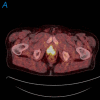

Prostate cancer is a common cancer in men and continues to be a major health problem. Imaging plays an important role in the clinical management of patients with prostate cancer. An important goal for prostate cancer imaging is more accurate disease characterization through the synthesis of anatomic, functional, and molecular imaging information. Positron emission tomography (PET)/computed tomography (CT) in oncology is emerging as an important imaging tool. The most common radiotracer for PET/CT in oncology, (18)F-fluorodeoxyglucose (FDG), is not very useful in the imaging of prostate cancer. However, in recent years other PET tracers have improved the accuracy of PET/CT imaging of prostate cancer. Among these, choline labeled with (18)F or (11)C, (11)C-acetate, and (18)F-fluoride has demonstrated promising results, and other new radiopharmaceuticals are under development and evaluation in preclinical and clinical studies. Large prospective clinical PET/CT trials are needed to establish the role of PET/CT in prostate cancer patients. Because there are only limited available therapeutic options for patients with advanced metastatic prostate cancer, there is an urgent need for the development of more effective treatment modalities that could improve outcome. Prostate cancer represents an attractive target for radioimmunotherapy (RIT) for several reasons, including pattern of metastatic spread (lymph nodes and bone marrow, sites with good access to circulating antibodies) and small volume disease (ideal for antigen access and antibody delivery). Furthermore, prostate cancer is also radiation sensitive. Prostate-specific membrane antigen is expressed by virtually all prostate cancers, and represents an attractive target for RIT. Antiprostate-specific membrane antigen RIT demonstrates antitumor activity and is well tolerated. Clinical trials are underway to further improve upon treatment efficacy and patient selection. This review focuses on the recent advances of clinical PET/CT imaging and RIT of prostate cancer.